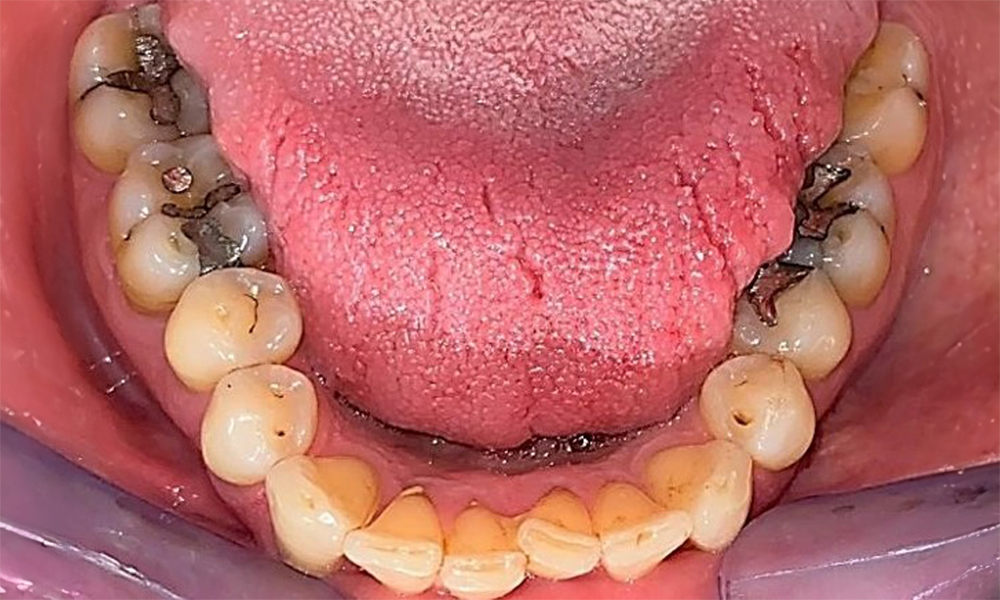

Der Patient hat ein vollbezahntes Gebiss mit 28 Zähnen, an welchen sich im Molaren- und Prämolarenbereich Amalgamfüllungen und Compositefüllungen befinden. An Zahn 14 zeigt sich ein sichtbarer klinischer Randspalt. Zahn 27 hat ein suffizientes Goldinlay. Zudem zeigen sich generalisierte Attritionen und Abrasionen. (Abb. 2, Abb. 3, Abb. 4, Abb. 5, Abb. 6)

Der Patient hat eine Parodontitis Stadium II, Grad B (5). Die klinischen Sondierungstiefen liegen mit 1-3mm im physiologischen Bereich. Lokalisierte Sondierungstiefen finden sich an 17 und 27 jeweils mesiopalatinal mit 5mm. Es liegen generalisierte Rezessionen von 1-3mm vor mit partiellem Verlust der Interdentalpapillen (Abb. 2, Abb. 3, Abb. 4)